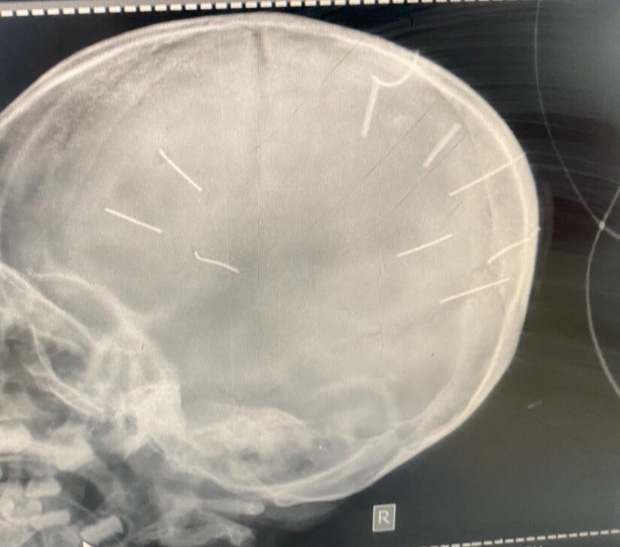

Sau khi thăm khám, các bác sĩ chẩn đoán bệnh nhi bị viêm màng não nên chuyển bé lên Bệnh viện Đa khoa Xanh Pôn. Theo ông Kiên, Bệnh viện Đa khoa Xanh Pôn đã tiến hành chụp cắt lớp dựng hình, nhận thấy có những hình ảnh giống những đinh gỗ ở sọ và tổ chức não, tổng cộng 9 cái.

Hình ảnh chụp X-Quang hộp sọ bé gái với 9 hình thể nghi là đinh (Ảnh: Bệnh viện Đa khoa huyện Thạch Thất cung cấp)